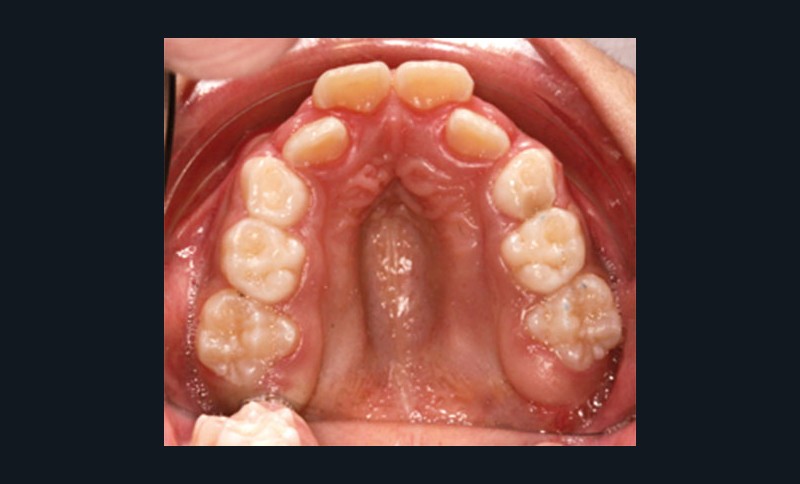

Au niveau dentaire, on évaluera la forme des arcades, la profondeur et l’étroitesse du palais, les malpositions et l’occlusion dans les trois sens de l’espace (fig. 2).

Certains phénotypes faciaux prédisposeraient au risque de troubles obstructifs du sommeil ; on décrit ainsi chez près de 34 % des enfants apnéiques une rétroposition mandibulaire, une hyperdivergence mandibulaire et un palais osseux ogival et profond.

Les dysmorphoses de ces jeunes patients s’accompagnent fréquemment de malocclusions dentaires, car, d’une part, l’insuffisance de développement des maxillaires occasionne un manque de place pour les organes dentaires, et, d’autre part, l’enfant adopte une posture linguale et mandibulaire de compensation, à l’origine d’anomalies secondaires.